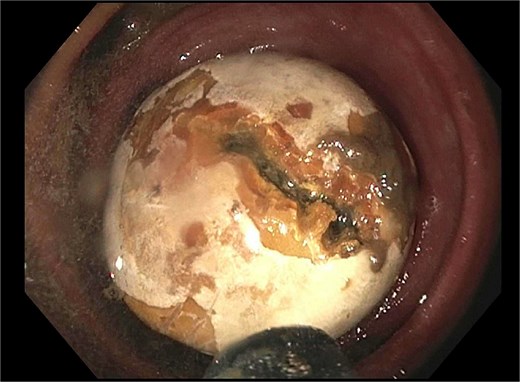

He re-presented 10 days later with nausea, vomiting, and obstipation. CT imaging showed large bowel dilation and a 3–4 cm gallstone lodged in the proximal sigmoid colon (Fig. 2). Flexible sigmoidoscopy confirmed the presence of the stone at a diverticular stricture (Fig. 3). Initial endoscopic retrieval attempts using snare, Roth net, and EHL failed.

Endoscopic view of gallstone impacted at diverticular stricture.